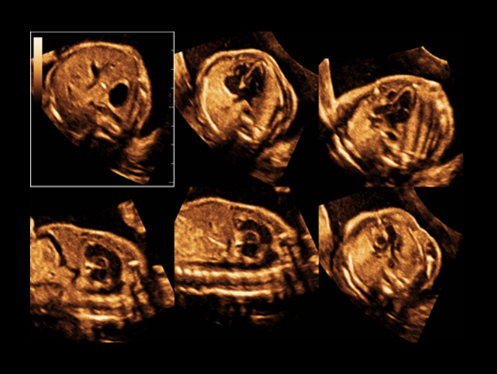

W aparacie DC-80A X-Insight zintegrowano inteligentne rozwi?zania z profesjonalnymi narz?dziami diagnostycznymi w ró?nych aplikacjach i podczas ca?ego cyklu badań: od pocz?tku ci??y, poprzez badania prenatalne, a? po opiek? poporodow?.

Obrazy kliniczne